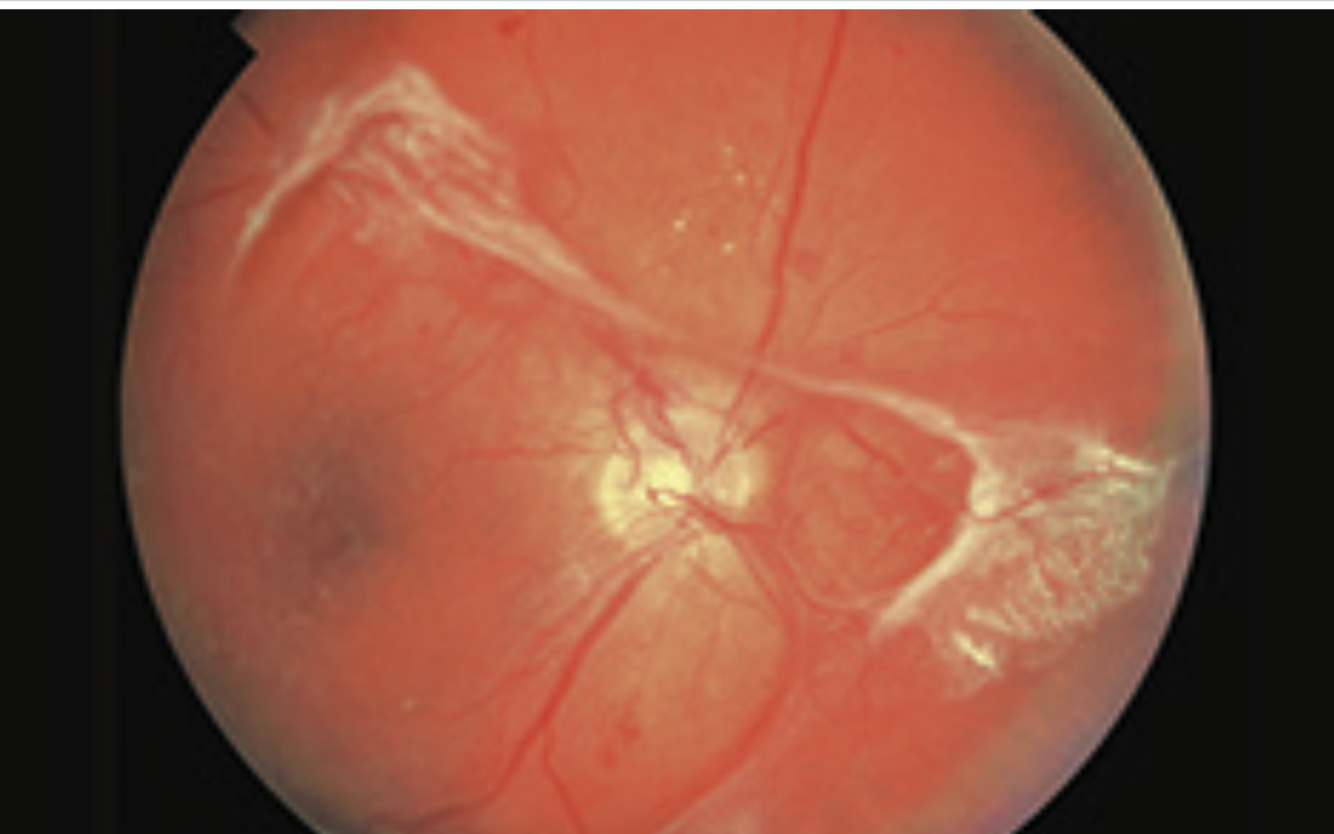

Advanced proliferative diabetic retinopathy

- hard exudates

-haemorrhages

-neovascularisation